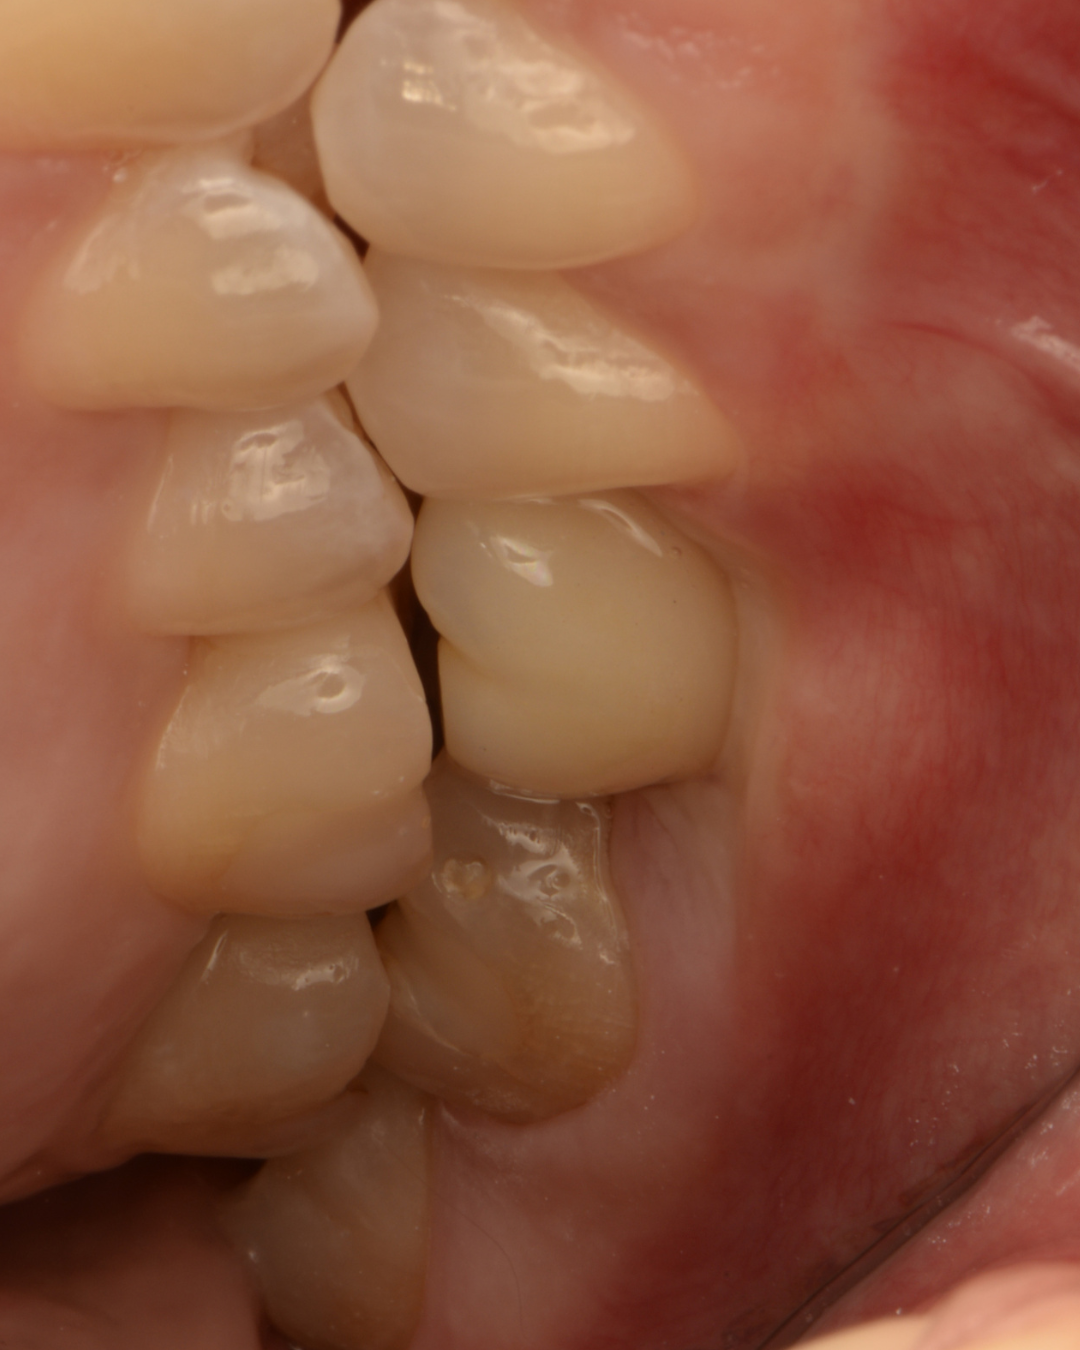

Складна негайна імплантація з кістковою пластикою

Олена, 30 років

Запальний процес у ділянці зуба внаслідок ускладненого карієсу та інфекції в кореневих каналах після перелікування. Значний дефект кісткової тканини з формуванням кістозного ураження та сполученням із гайморовою пазухою, що ускладнювало можливість негайної імплантації.